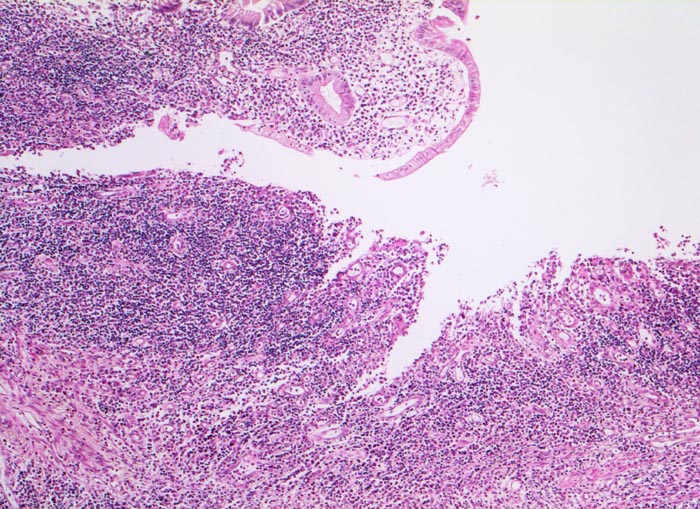

PathoPic ID 5085 - Morbus Crohn

Morbus Crohn

Entzündung / Reparatur

Ileum terminal

Darm, Anus

Subakutes Ulkus mit

Granulationsgewebsbildung.

Verplumpung der entzündlich infiltrierten Dünndarmzotten.

Bekannter Morbus Crohn. Resektion des terminalen Ileum wegen mechanischem Subileus und enterokutaner Fistelbildung.

Histologie

50

27

männlich